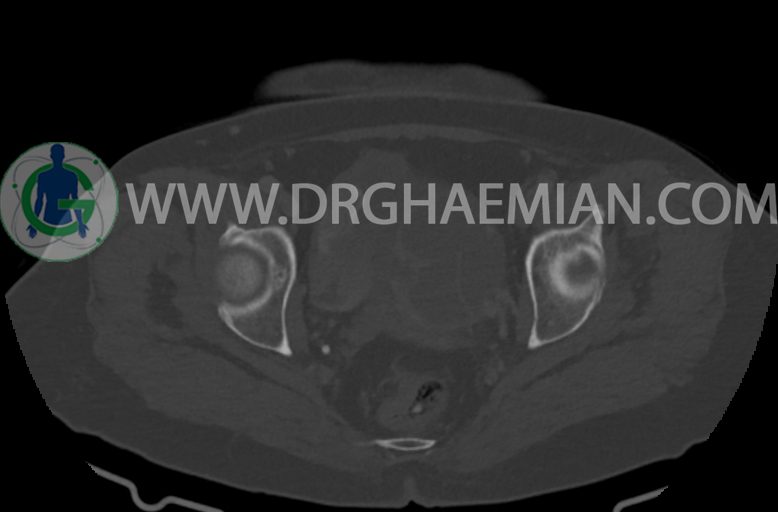

سی تی اسکن شکم و لگن با استفاده از اشعات ایکس تصاویر عرضی از ناحیه شکم و لگن ایجاد میکند. در این کیس موسینوس کیست آدنوما، شواهد هیسترکتومی، ضایعه در سمت راست لگن، کیست در کبد و … دیده می شود.

–ساختار Cystic multiseptate همراه با Enhancing thick septation به ابعاد 79x62mm در

لگن دیده می شود که در درجه اول مطرح کننده ی ضایعات نئوپلاستیک تخمدانی نظیر mucinous cyst adenocarcinoma است.

–ضایعه ی mass like هیپردنس- هتروژن به قطر 42mm در سمت راست لگن